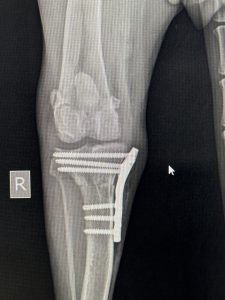

Hirurško liječenje rupture prednjeg križnog ligamenta koljena - TPLO

Za razliku od tradicionalnih metoda koje pokušavaju zamijeniti ili rekonstruisati ligament, TPLO mijenja biomehaniku koljena. Tokom zahvata, hirurg reže tibijalnu ploču (gornji dio goljenične kosti) i rotira je pod precizno izračunatim uglom kako bi se smanjio nagib zgloba. Time se eliminira klizanje femura po tibijalnoj ploči, koje nastaje zbog puknuća ligamenta, i stabilizira koljeno bez potrebe za ligamentom.

TPLO je postao zlatni standard u liječenju ove vrste povreda, pružajući ljubimcima priliku za bezbolan i aktivan život.